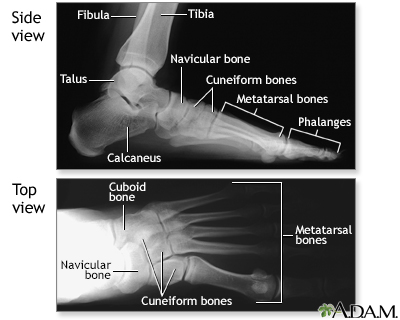

Normal foot x-ray